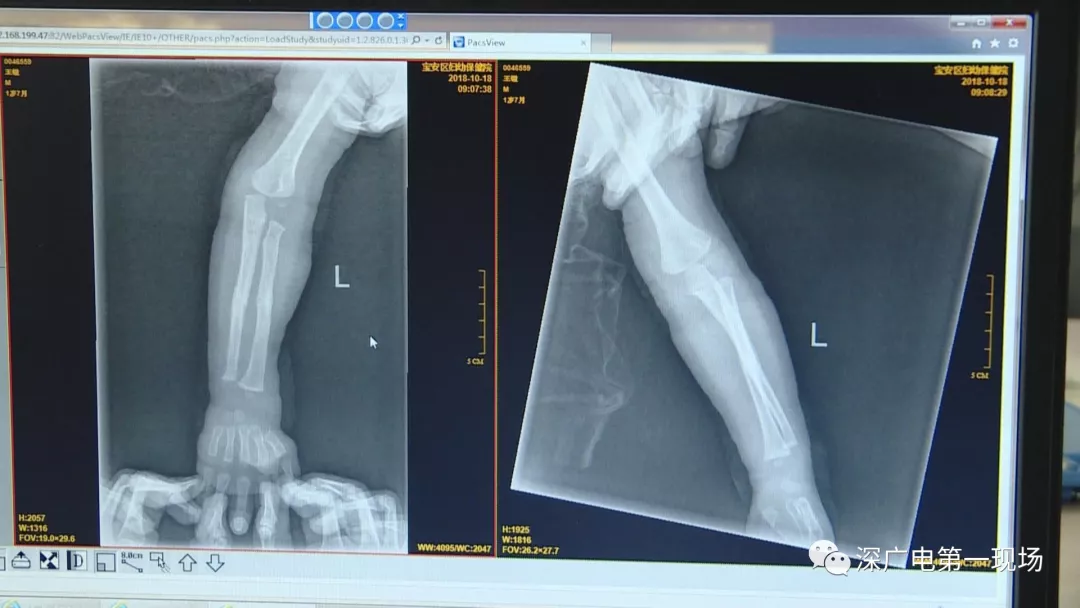

因祸得福!1岁男童摔伤送院 医生竟从胸片中发现了这个…

胳膊摔骨折胸片里发现异物